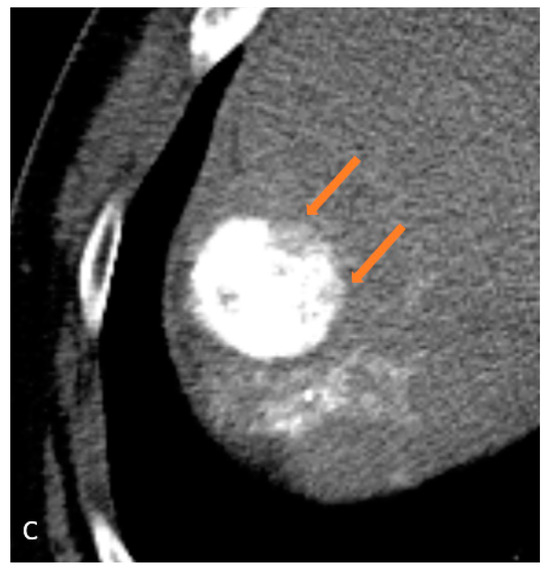

| 7 | CEUS | Target | LR-treated | CT called residual tumor, follow-up CT showed the area was perfusional, not disease (Figure 3) |